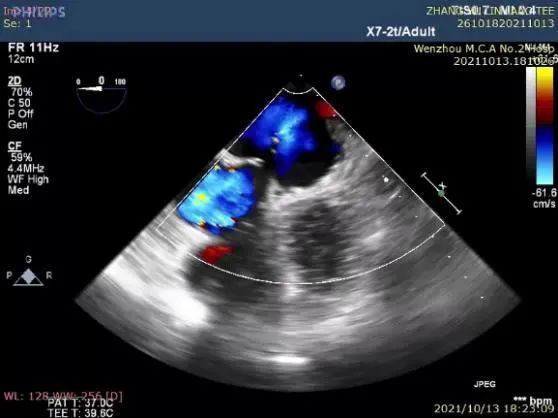

完全展开封堵器后评估:封堵盘此时置于嵴内,不符合预期。李教授通过牵拉操作,使封堵盘成功盖在嵴外,且固定盘锚定良好,非常稳定。释放后再次评估,超声及造影证实封堵器恰能完全覆盖心耳,满足COST原则,结束手术。

图8:TEE评估图

图9:释放封堵器

图10:释放后TEE再次评估封堵效果